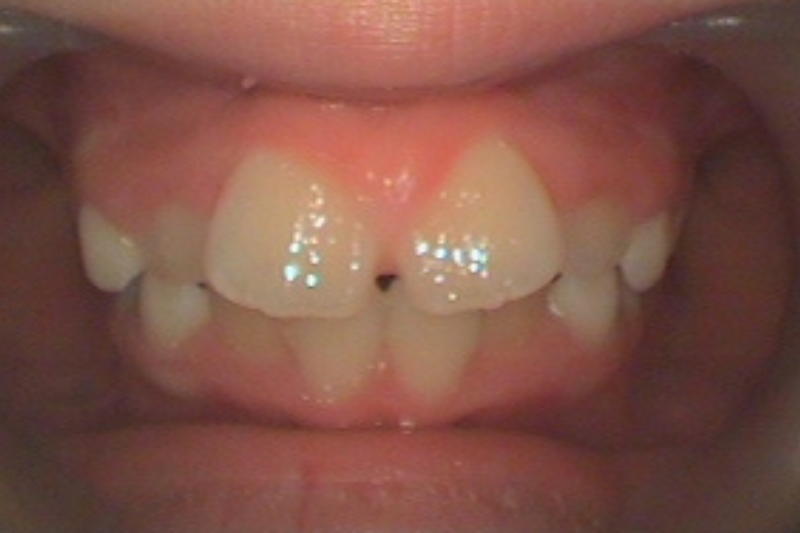

症例1

Before

症例1 治療前

After

症例1 治療後

年齢・性別 11歳・女の子

治療内容 マイオブレイス

治療期間 5年6ヶ月(予防期間含む)

費用 400,000円(税込)

主なリスク 矯正装置の装着時に違和感や痛みが生じる場合があります。

装置の使用状況により治療期間が延長する場合があります。

治療後、保定装置を使用しない場合は後戻りする可能性があります。

治療結果には個人差があります。